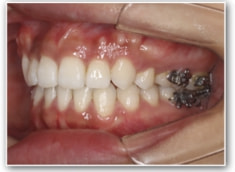

叢生+左下1番先天欠如ケース

治療法:裏側の矯正(リンガルブラケット:舌側矯正)

治療前